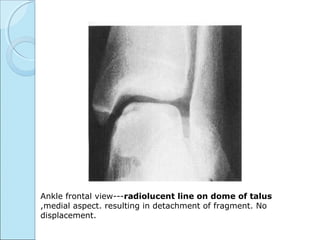

Ankle frontal view---radiolucent line on dome of talus

,medial aspect. resulting in detachment of fragment. No

displacement.